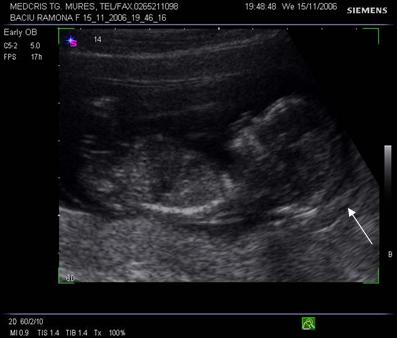

Fig. nr.112 Sarcina 12 saptamani la ecografia transvaginala